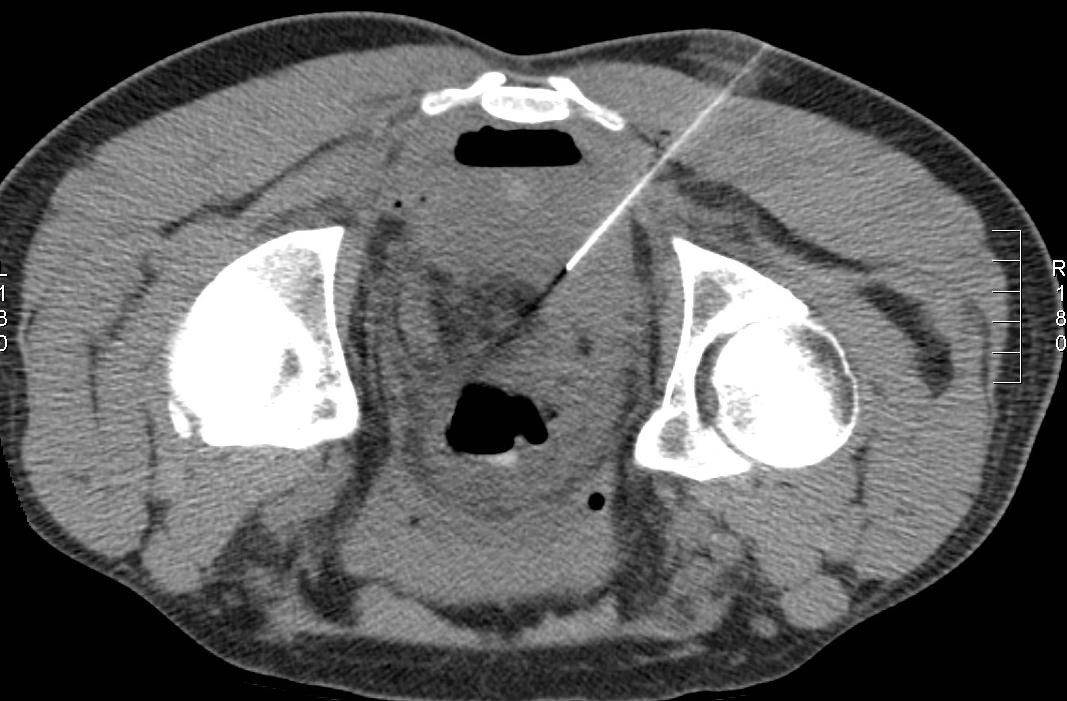

右侧14F多用途引流导管

骶前积液明显减少